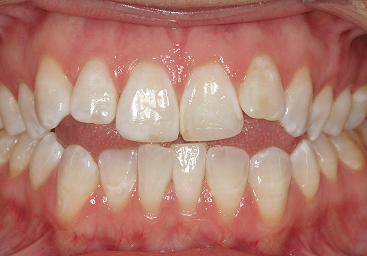

A lot of people have crowding of their teeth. In fact, this is one of the most common things we see here. This patient of ours had moderate upper and lower crowding.